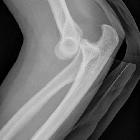

Plain radiograph

The dislocation is usually obvious, especially if adequate AP and lateral views are obtained, however, the challenge is in identifying associated fractures.

Although rarely required in practice, a line drawn along the anterior margin of the humerus (anterior humeral line) and one along the long axis of the radius should intersect near the center of the capitellum .

- dislocation direction

- posterior, posterolateral, posteromedial, lateral, medial or divergent

- associated fractures

- most frequently the radial head and coronoid process

- other fractures encountered include medial epicondyle (in children), lateral condyle, capitellum, olecranon